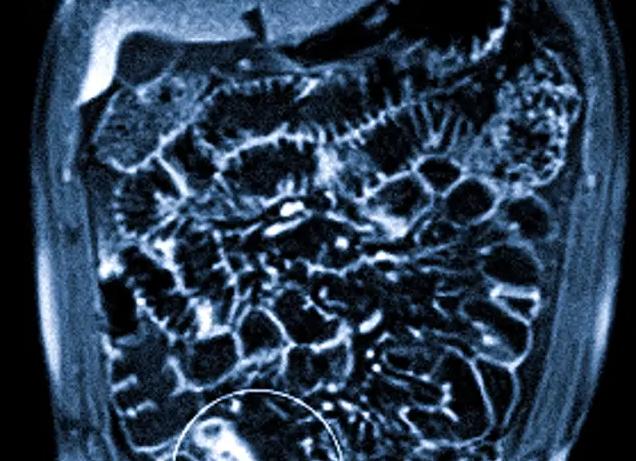

МРТ коленных суставов

Коленный сустав очень уязвим. Ему приходится выдерживать значительные динамические нагрузки. Болевой синдром в коленях беспокоит многих людей, но чаще всего с ним сталкиваются спортсмены и люди преклонного возраста. Иногда для выяснения причины появления болей и хромоты не обойтись без МРТ коленного сустава. Поэтому пациенты хотят знать, что такое МРТ коленного сустава и как его делают.